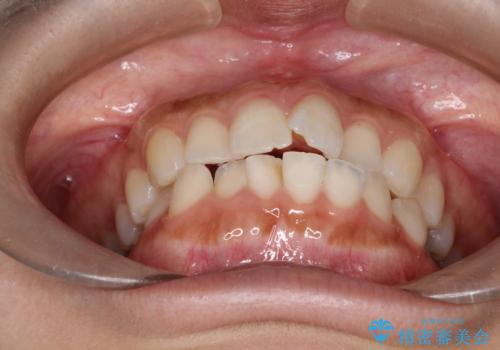

- 口元が出てるのが気になるとのことで来院されました。

上下左右前から4番目の歯を抜歯して前歯を後方に下げて、口元を下げる計画としました。

口元を大きく改善したい場合は抜歯が必要となることが多いです。